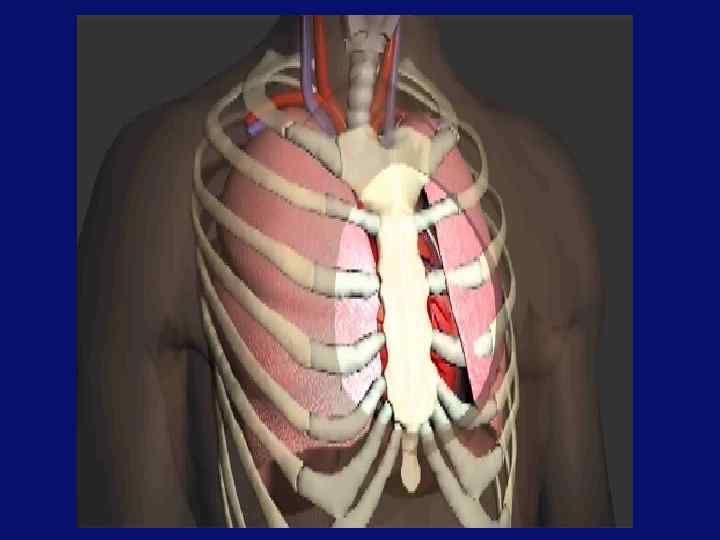

Моделирование потоков